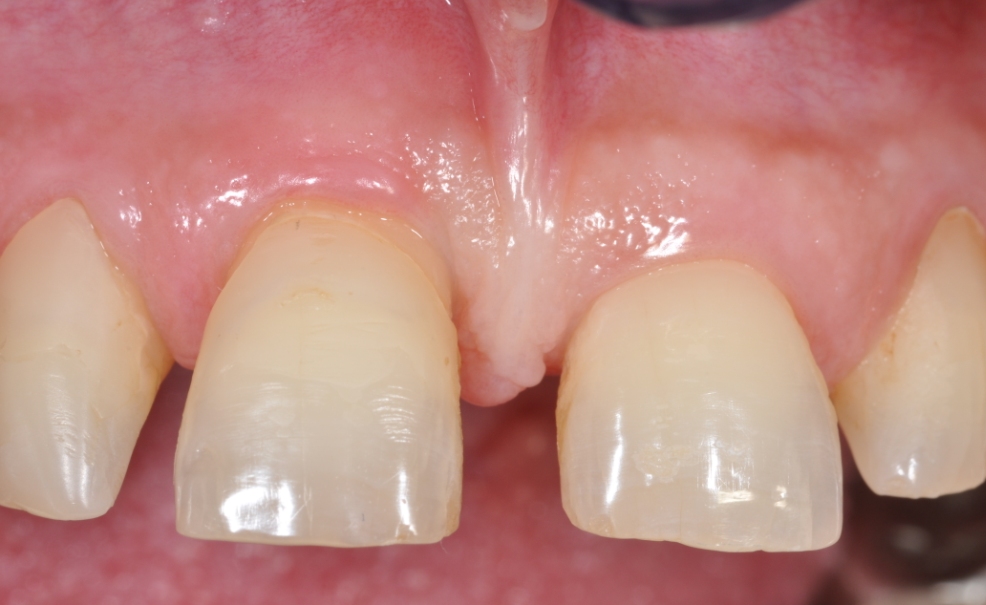

Immediate implant placement in the maxilla with contour GBR - Dr. K. Loukas

The patient presented with a terminal fracture of the crown tooth number 12